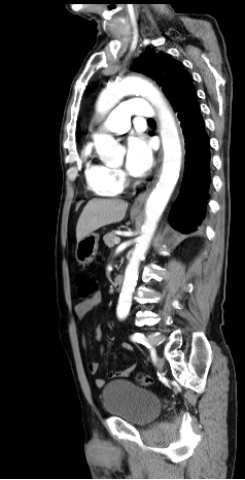

3. 82歲老婦人到院主訴五天來有日趨嚴重的呼吸困難。病史顯示30年前就有醫師告知心臟雜音,因無症狀,未曾有任何治療。近五年來運動耐受逐漸不佳,且偶有突發性悸動及心絞痛,特別在步行樓梯間更加惡化。住院當日清晨3點突然重度呼吸困難,因而急診住院。理學檢查:血壓110/62 mmHg;心跳90/分;頸靜脈怒張。心臟大小正常,但在右上胸骨緣及心尖部有Gr III/VI systolic murmur, S2減輕:其他所見尚無異常。其胸部X光、心臟超音波及心電圖如圖。WBC,5.2 k/micro L;AST,21U/L;CK,111U/L;CK-MB,14.6U/L;Troponin I,0.06 ng/ml。請問下列何項處置最恰當? (A) Percutaneous coronary intervention (B) Aortic valve replacement (C) Nitroglycerin IV infusion at the rate of 15mcg/min (D) Titrate PO carvedilol starting from 3.125 mg and reassess in 3 months (E) Treating with IV digoxin 0.125mg in conjunction with IV bolus Furosemide 20mg and then 20 mg BID

Estimated aortic valve area = 0.37 cm2 With the peak Ao flow at 580 cm/sec ; the peak pressure gradient at 134mmHg and the LVEF (56%)